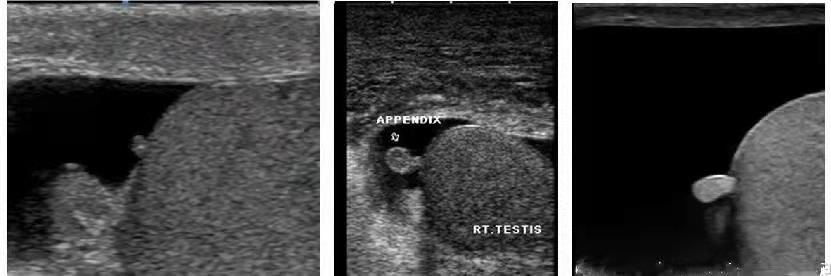

睾丸附件扭转的超声图像及表现

超声表现主要为:①患侧阴囊壁水肿,附件肿大,回声欠均或不均;②扭转的附件位于附睾头旁、睾丸上极或附睾头与睾丸上极之间,以后者多见;③附件附着处轻度肿大,回声增强,附着处组织血供增多,而附件内无血流信号;④扭转后可发生囊性变、钙化、脱落。

超声因其无创、快捷、准确、可重复性强等优点,成为诊断该病的最佳检查方法,诊断睾丸附件扭转超声须探及直接征象,结合病史、症状、体征,诊断率可大大提高。